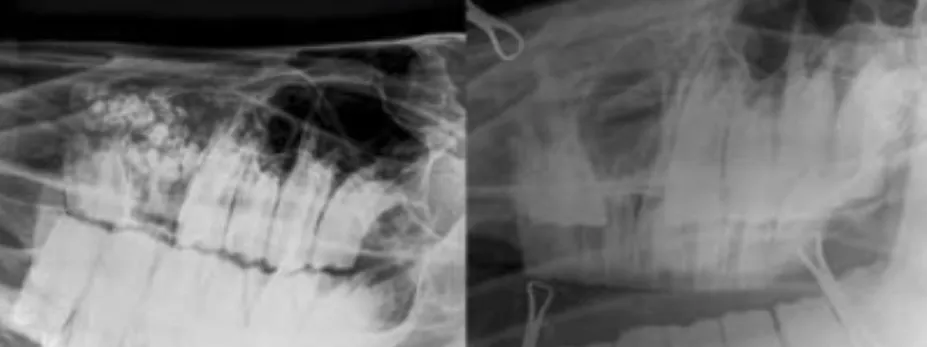

Radiography

The x-ray facilities available at the R(D)SVS permit radiographic examination of the chest of adult horses, a procedure which requires powerful equipment and skilled personnel. This technique allows assessment of the lung not accessible by endoscopic examination or airway sampling, such as the non-airway component of the lung.